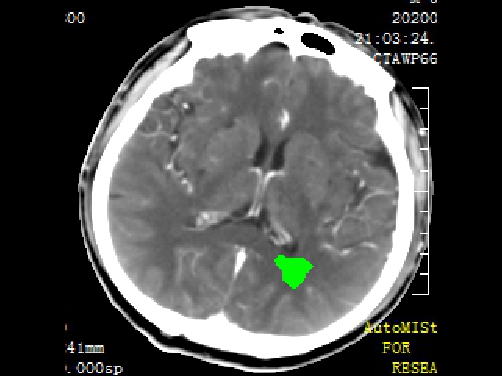

急诊予以静脉溶栓,同时完善头颈CTA+CTP、MIStar相关检查

结合CTA结果,提示左侧颈内动脉起始部至颈内动脉末端未见显影,起始部成鼠尾征改变,前交通动脉开放,双侧大脑中动脉显影良好。MIStar图像提示核心梗死灶和缺血半暗带较小,但是MTT提示左侧大脑中动脉流域区明显延长。